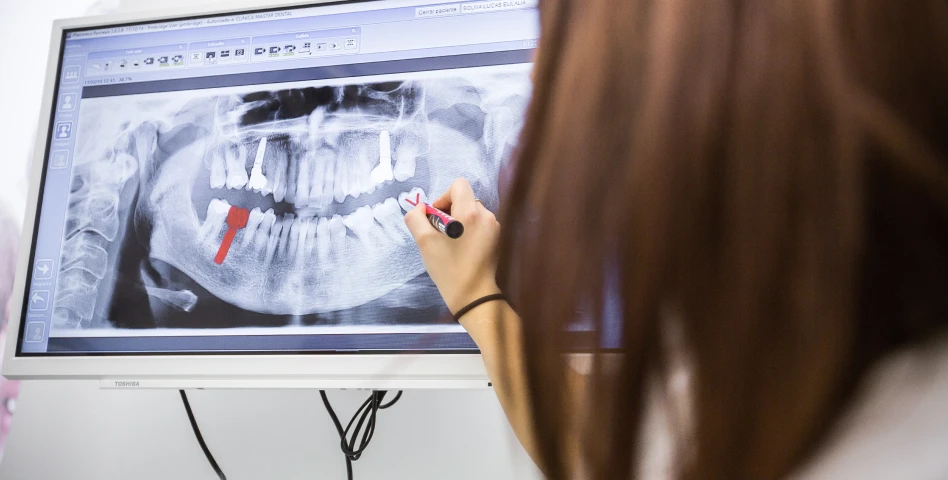

La plupart des patients, sauf contre-indications médicales sévères. Un bilan préalable (scanner, examens médicaux) est indispensable.